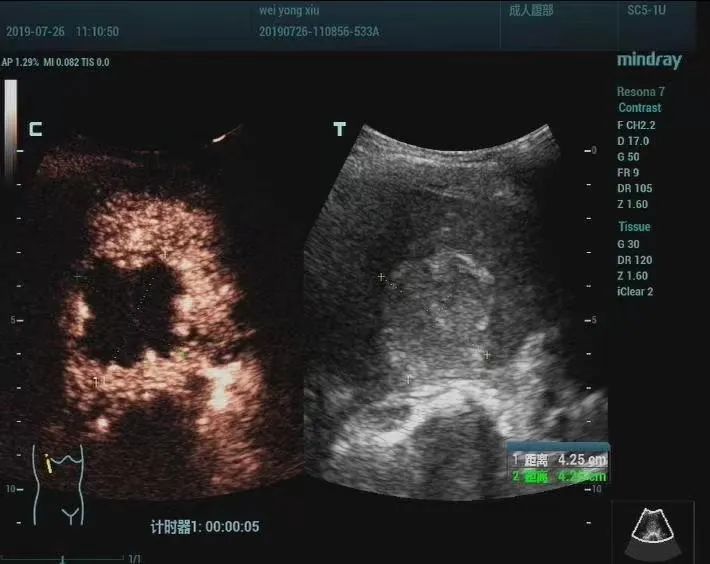

5.超声声学造影及三维、四维立体成像技术——超声声学造影被誉为“无创性微循环血管造影”,具有高准确性、高安全性、操作简便、重复性好的特点。适应症:①肿瘤定性(良、恶)诊断;②微小病灶早期发现;③介入治疗后的疗效评估。二维是平面成像,三维是立体成像,四维是三维加上时间的维度,即动态的三维,通过表面成像模式、骨骼成像模式、血管成像模式等由计算机进行三维重建。